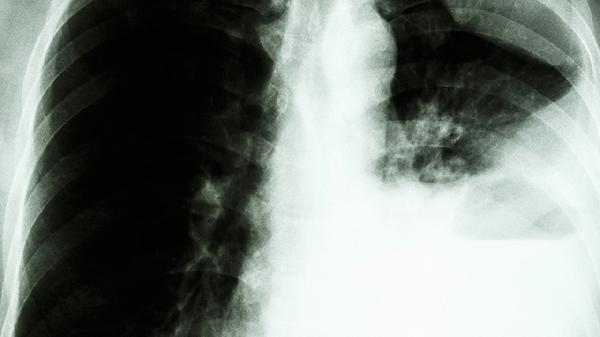

流行型肺孢菌病有哪些表现

流行型肺孢菌病主要表现为发热、干咳、呼吸困难、胸痛、乏力等症状。流行型肺孢菌病是由肺孢菌感染引起的呼吸道疾病,可能由免疫功能低下、长期使用免疫抑制剂、艾滋病病毒感染、恶性肿瘤、器官移植等因素引起。

呼吸困难是流行型肺孢菌病的严重症状,表现为呼吸急促、气短、活动后加重。呼吸困难可能与肺孢菌感染导致的肺泡损伤和肺功能下降有关,患者可能出现口唇发绀等缺氧表现。针对呼吸困难症状,可在医生指导下使用氨茶碱片、沙丁胺醇气雾剂、布地奈德福莫特罗粉吸入剂等药物进行平喘治疗。

胸痛是流行型肺孢菌病的伴随症状,多表现为胸部隐痛或刺痛,咳嗽时加重。胸痛可能与肺孢菌感染引起的胸膜炎症或肺实质病变有关,患者可能伴有深呼吸受限。针对胸痛症状,可在医生指导下使用双氯芬酸钠缓释片、塞来昔布胶囊、洛索洛芬钠片等药物进行止痛治疗。